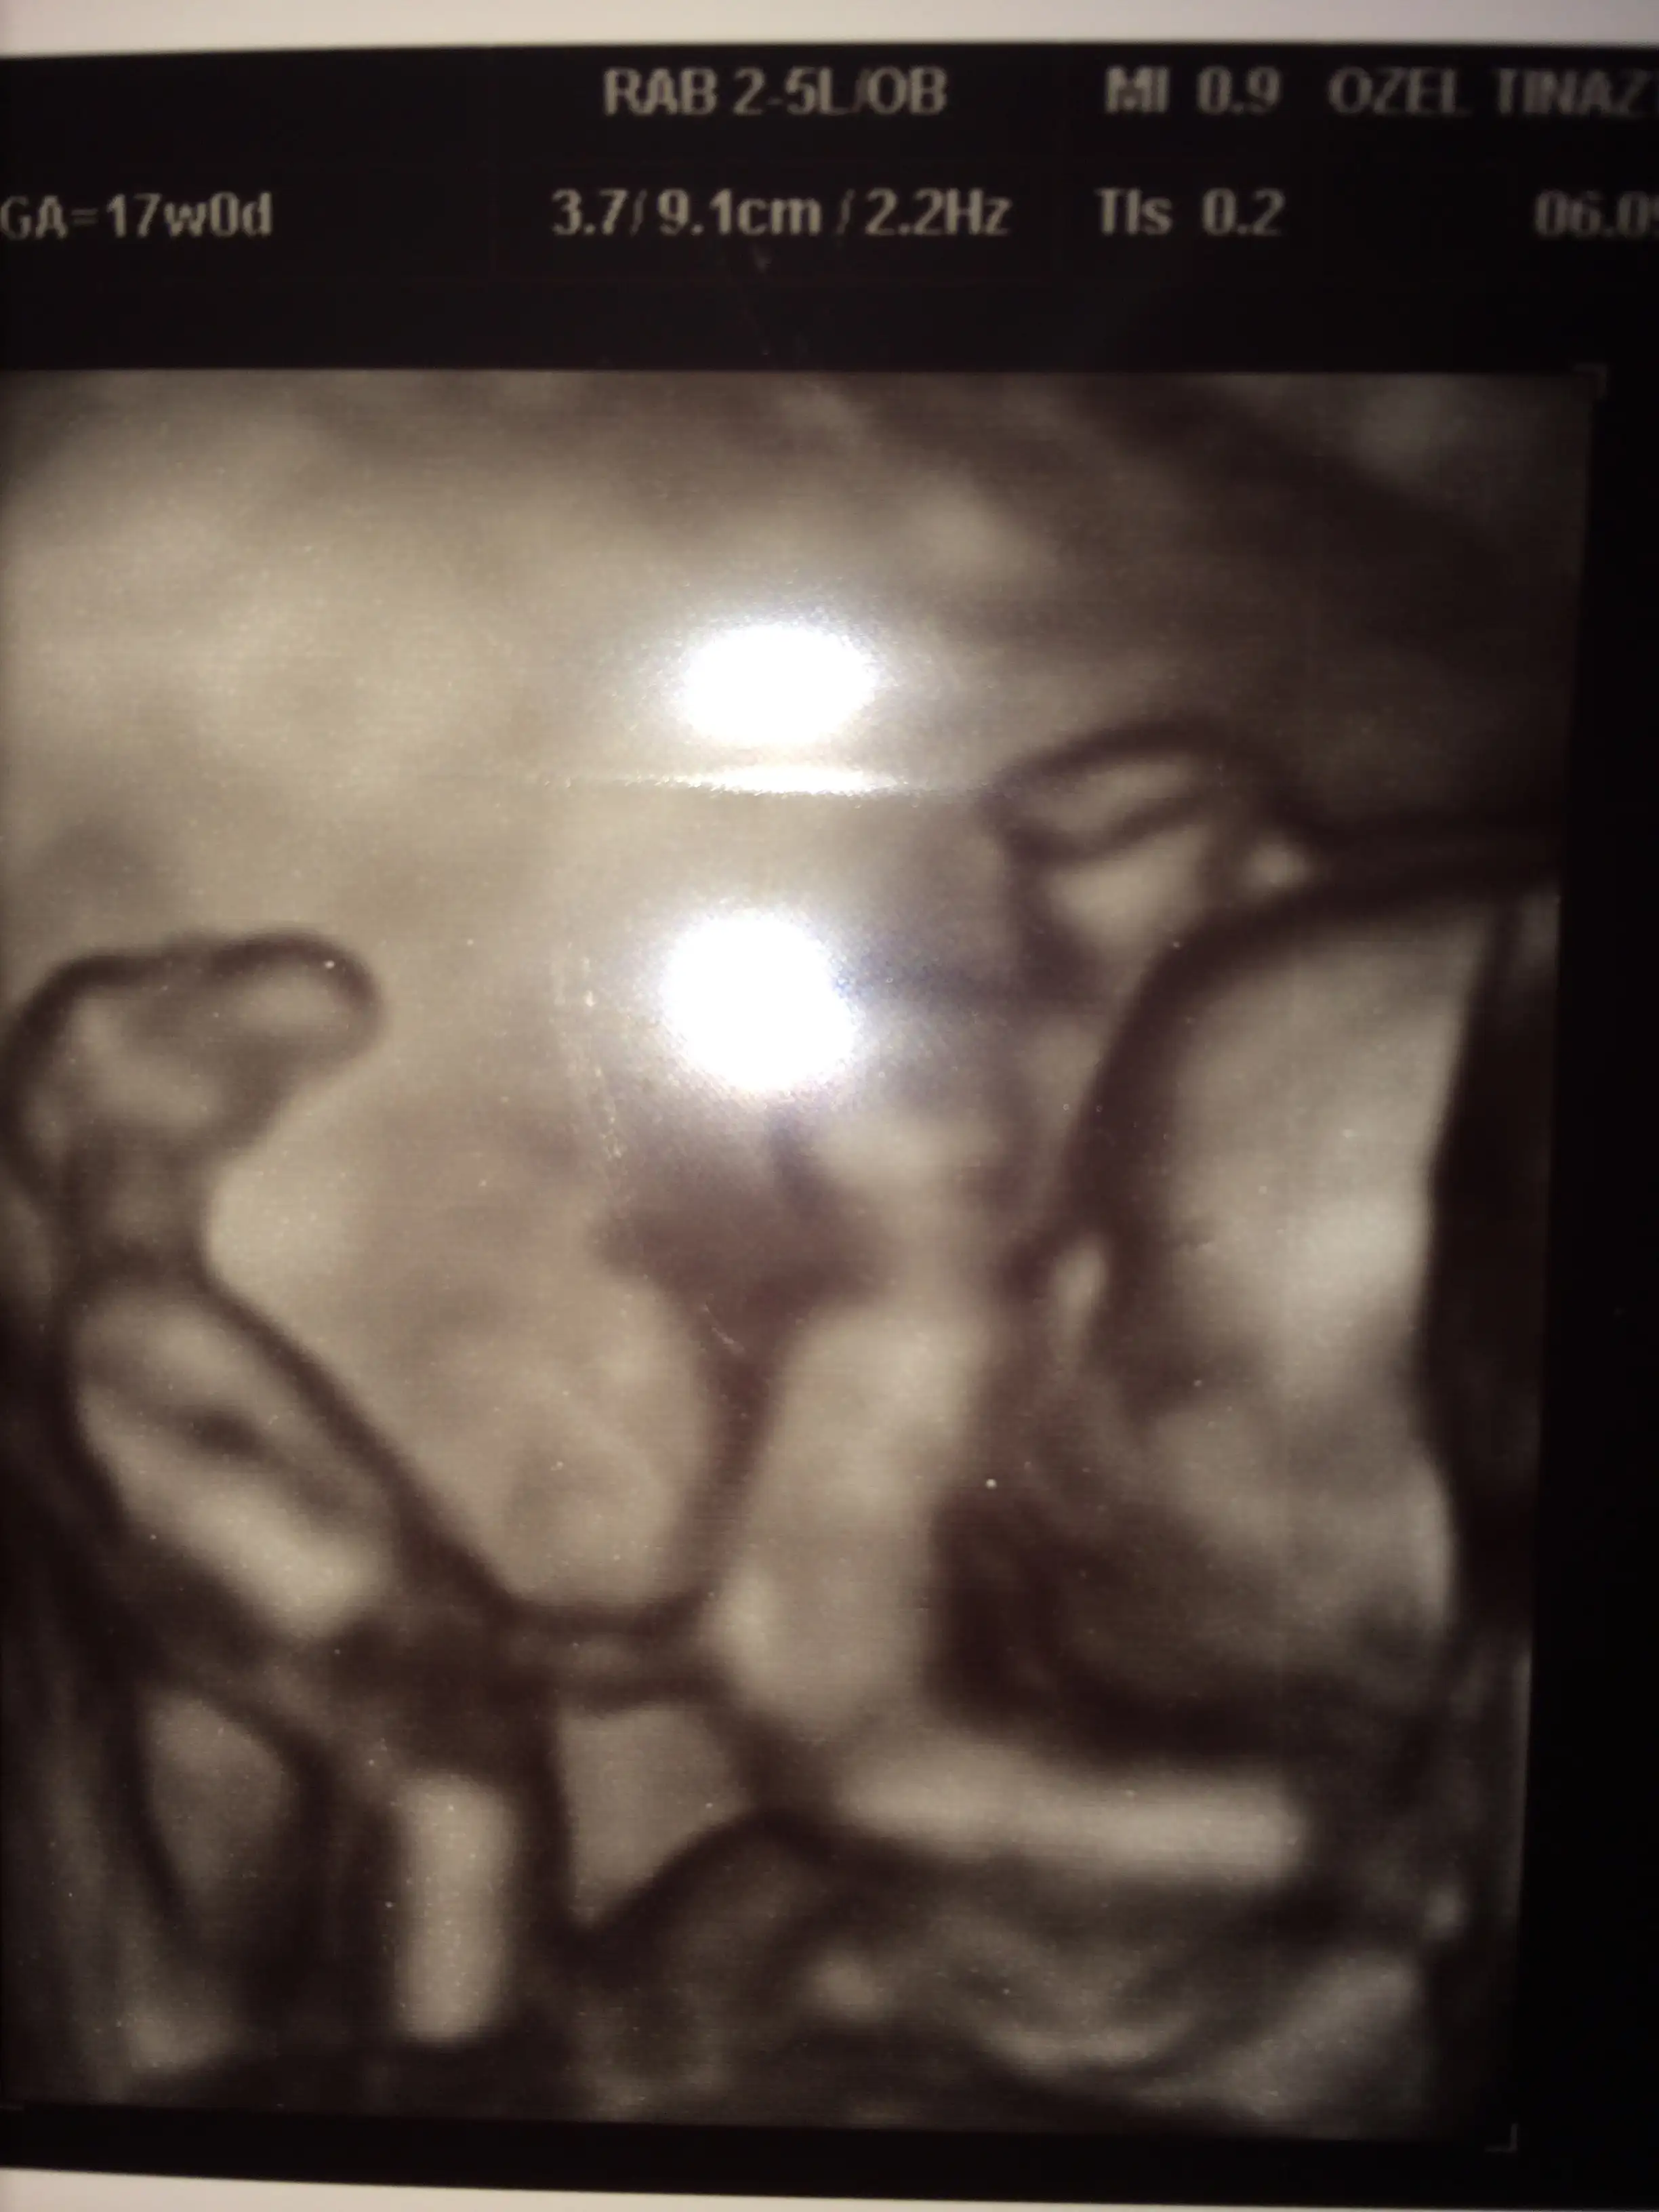

saol canım alah hepimizin bebeğine sağlık versin.ah masallah kuzumaane kadar da belırgın cıkmıs ve kocaman olmus resmen. ah ya acayıp duygulandım resmen çizilmiş gibi. bebegım benım ya . bu ayrıntılı resmi öi normal ultrason mu? ah kuzular kocaman oluyor artık ...

Masallah subanallahhBakın Buda benim kızçem :) maşallah kuzuma

kolunu emiyomuş dr öle dedi :)Masallah subanallahhyerim inu nasilda ellerini kaldirmis ya kuzucuk

saol canım alah hepimizin bebeğine sağlık versin.canım bunu normal muayenede çekti 4 boyutluymuş ama ben biraz çakalık yaptım sanırım doktora dedim ki bana yüzünü gösterirmisiniz dedim biraz fazla hareketli bizim cadı durmuyo bakılırken ben öle diyince hemen 4 boyutluya çevirdi daha öncede rapor versin diye ayakta duramıyom demiştim gaddar oluyolar çünkü istediklerini yaptırmak için çakal olman gerekiyo :)

ben resimden bir şey anlamadım. baktım baktım. bunu ne zaman çekti yeni mi?kolunu emiyomuş dr öle dedi :)

:) sen deki ona ilk önce yüzünü gösterirmisiniz o normalde göstermez zaten gösterir se de 4 boyutluda bakabiliyormusunuz de :) inşalah gösterir canımvalla dogru soyluyosun gercekte çakal olmak lazım. bı dahakıne bende istıycem boyle resım özendirik oldum